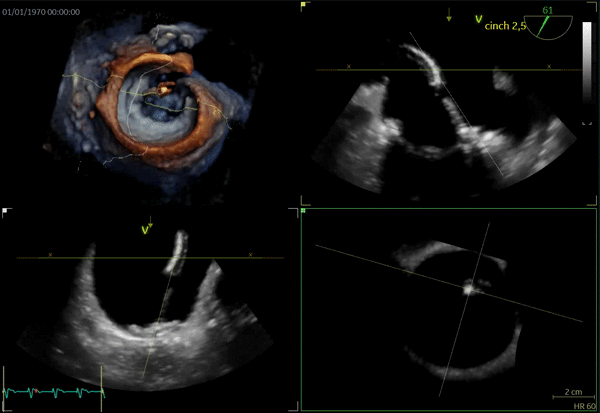

TMVR

- Cvi42 Mitral, distribuito da GE per Circle Cardiovascular, è un'applicazione leader che offre un set di strumenti e un flusso di lavoro completi per la valutazione della valvola mitrale. Accessibile solo su AW 4,7. Cvi mitral è venduto separatamente. Potrebbe non essere disponibile in tutti i mercati. Contattate il rappresentante commerciale locale

- 15596_MVQ_Whitepaper_v7.pdf